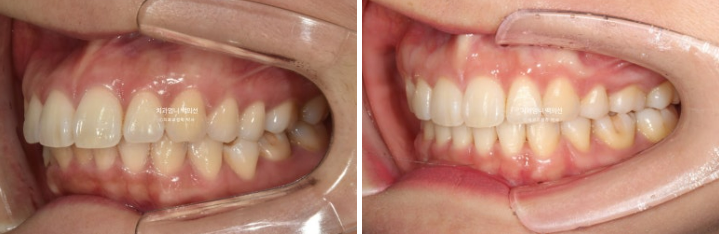

22년 9월, 교정치료를 위해 오신 30대 환자분입니다.

앞니 돌출에 의한 뚱한 인상 개선과 입술이 잘 안다물어짐을 고치고자 오신 분입니다.

작은어금니 4개 발치교정 권유드리고 치료에 들어갔고 클리피씨 교정을 선택하셨습니다.

돌출입 발치교정 입술부전증 치료 후 교합도 좋습니다.

전 후 비교 보겠습니다.

22.09~25.04